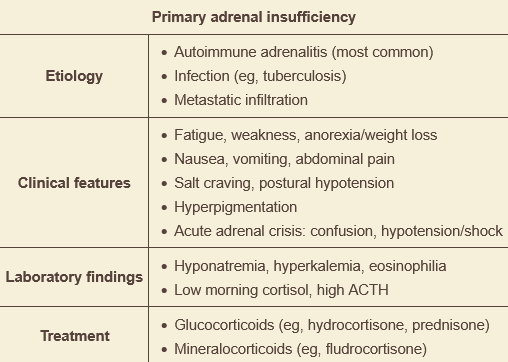

weakness, lightheadedness, dry mucuous membranes, nausea, diffuse abdominal pain, weight loss, orthostatic changes, and hyperpigmented buccal mucosa. dx?

primary adrenal insufficiency